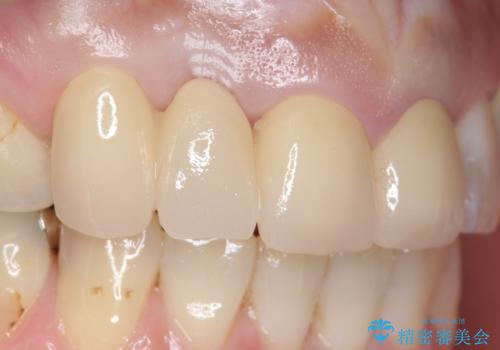

オールセラミッククラウン 下がってしまった前歯の歯茎の改善

- 他院で治療したところ、右上2番目の歯の歯茎が下がってしまったので診て欲しいといらっしゃった方の症例です。

診査の結果右上2は歯根が破折しており、それが原因で骨及び歯肉の吸収が起きていました。

このまま右上2の抜歯を行うとさらに歯茎が下がる恐れがあったため、歯の挺出によって骨レベルを回復した上で抜歯し、歯槽堤保存術(抜歯窩に人工骨を填入する手術)を行いました。

その後ブリッジによる補綴を行うことで、自然な見た目を再現することができました。